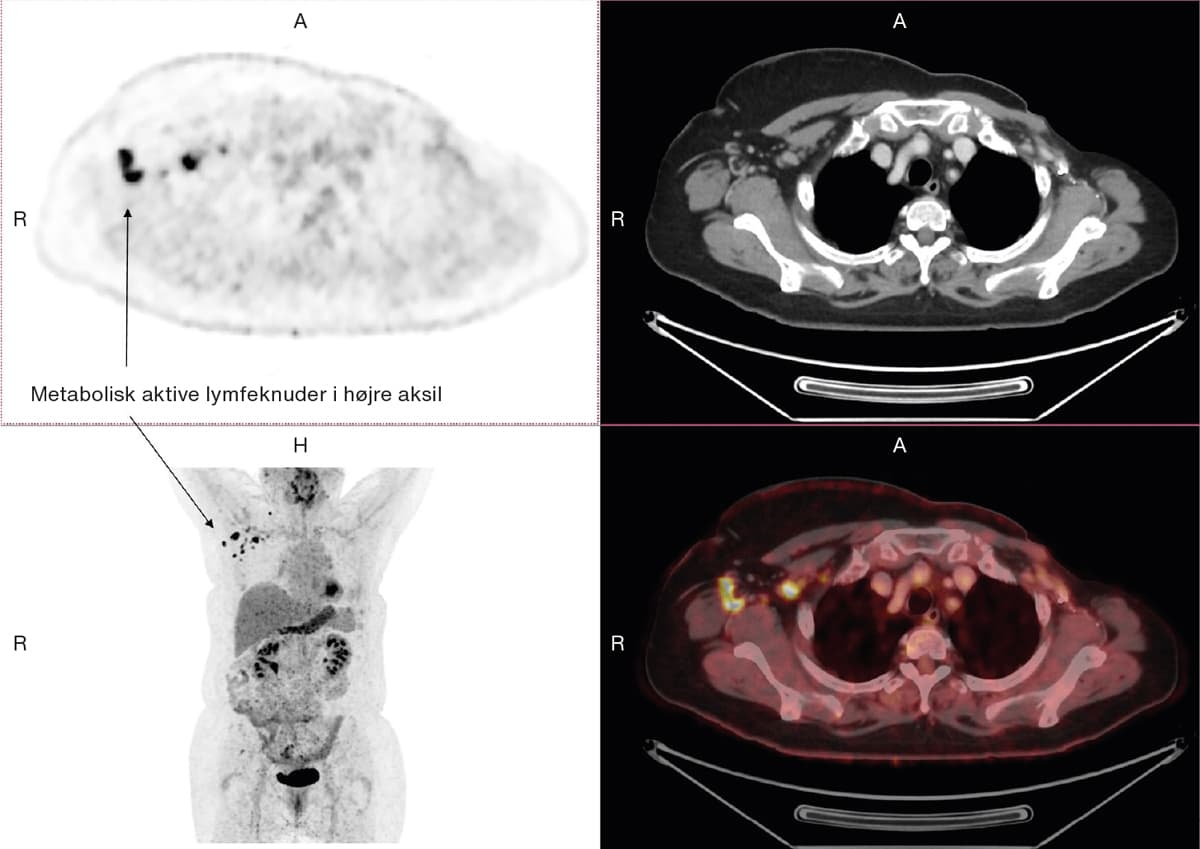

En 65-årig kvinde, der var radikalt mastektomeret for venstresidig mammacancer 20 år tidligere, søgte egen læge pga. ubehag nær venstre brystprotese. Ved en objektiv undersøgelse palperedes der en mulig fortykkelse af venstre costa 10-11. Der var mistanke om metastasering af tidligere cancer, og patienten blev henvist i et kræftpakkeforløb. Som led i udredningen blev der foretaget 18F-fluordeoxyglukose-positronemissionstomografi (FDG-PET)/CT. På skanningen sås flere lymfeknuder i højre aksil og supraklavikulært med kraftigt øget metabolisme, som det kan ses ved malignitet. Lymfeknuderne havde dog reaktivt udseende på CT-billederne med bevaret fedthilus. Der var i øvrigt ingen tegn på recidiv. Patienten var otte dage inden FDG-PET/CT’en blevet COVID-19-vaccineret i højre skulder med en mRNA-vaccine. Fundet blev tolket som lokal immunologisk respons på vaccinationen [1]. Efter udrulning af massevaccination mod COVID-19 er samtidige reaktive metabolisk aktive og forstørrede regionale lymfeknuder en vigtig differentialdiagnose at kende til ved mistanke om malign sygdom.